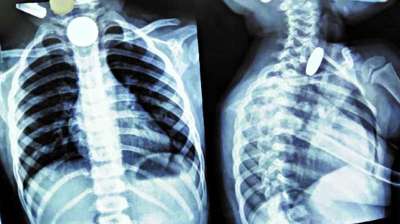

खिलौना नहीं सिक्का था! बच्चे ने निगले 5-10 रुपये के सिक्के, डॉक्टरों ने ऑपरेशन कर निकाले

24 Jul, 2025 04:09 PM IST | AVSNEWS.COM

दिल्ली : दिल्ली के एक सरकारी अस्पताल के डॉक्टरों ने 12 वर्षीय बच्चे की जान बचाई है। बच्चे ने पांच और दस रुपये के तीन सिक्के निगल लिए थे। सिक्के...